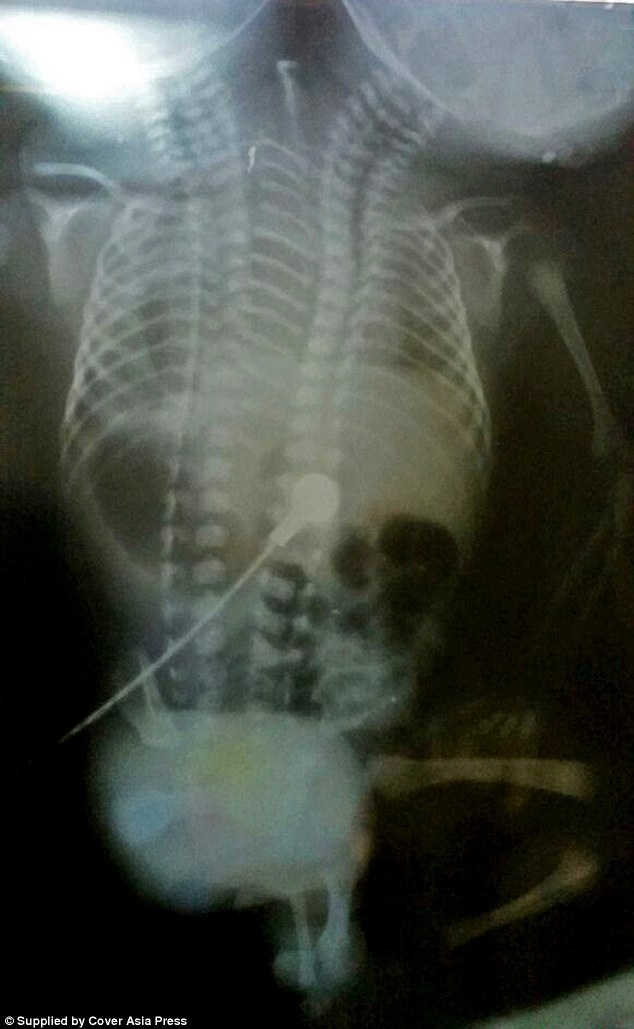

Mặc dù bề ngoài của em bé này có 2 đầu và một phần thân nhưng phim chụp X-quang cho thấy phần xương và các cơ quan nội tạng bên trong được tách rời. Các bác sĩ đã cân nhắc đến khả năng thực hiện phẫu thuật để tách rời 2 đứa trẻ nhưng ca dính liền quá phức tạp nên khả năng này là rất khó.

“Các ca phẫu thuật có thể được thực hiện trong một số ca sinh đôi dính liền, nhưng trường hợp này rất khó vì quá phức tạp và gần như không thể phẫu thuật”, bác sĩ Jai cho biết.

“Mặc dù cặp sinh đôi có đầy đủ cơ quan nội tạng tách rời nhưng chúng đều dính liền bên trong một cơ thể, với chỉ 2 chân và 2 tay. Vì thế, bạn không thể tách rời trẻ em đó.”.